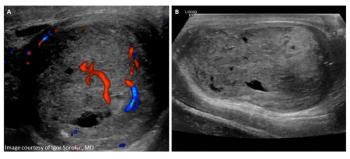

Quiz: Testicular trauma in 21-year-oldByChristine Van Horn, MD,Igor Sorokin, MDAugust 11th 2020A 21-year-old male presented to the emergency department for evaluation of testicular pain and swelling 5 days after being struck in the groin.